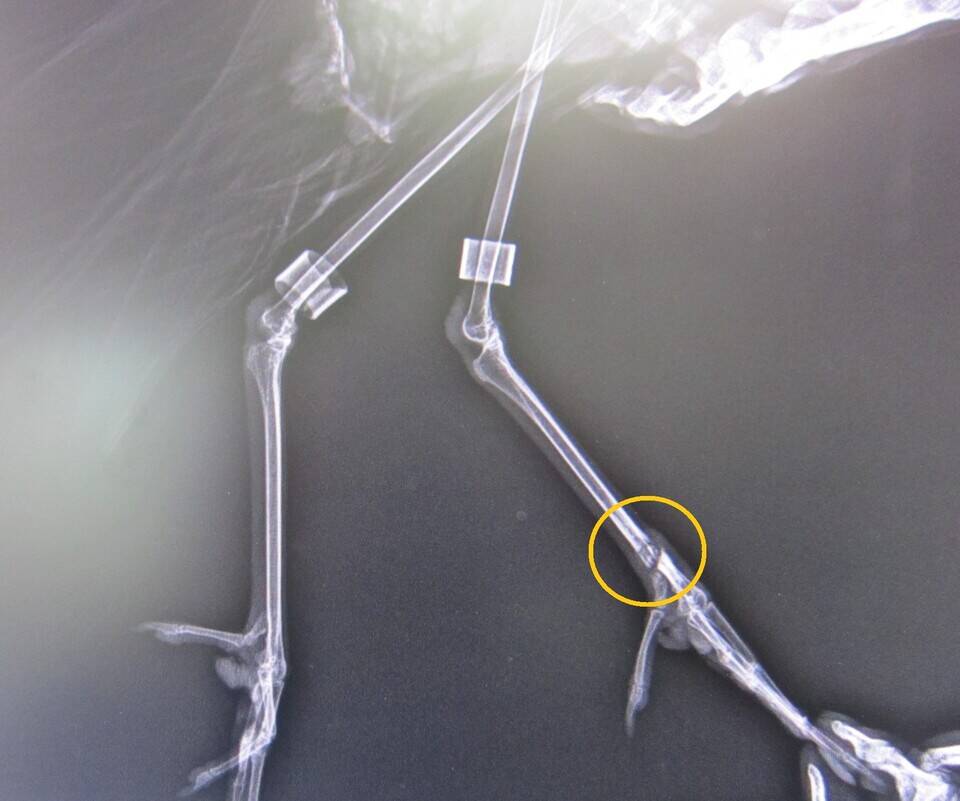

バードケージつながりでもう1枚。

これはブロンズトキの脚の写真です。

向かって右側が左脚で、ケガしたのもこの脚です。

さてどこが悪いのでしょうか?

左右の脚を見比べてみればすぐにわかるはず。

正解は・・・

はい、ここ、このふしょ骨という骨が折れていました。

重傷なので入院させ、しばらく副子(添え木のこと)をあててテーピングしていたところ、無事完治!

すでにバードケージに戻って、以前通りの生活を送っています。